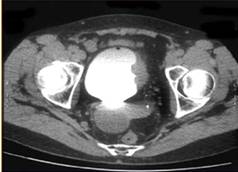

В комплексном обследовании больных опухолью мочевого пузыря в последние годы стали использовать и компьютерную томографию, с помощью которой можно уточнить глубину инвазии новообразования и состояние регионарных лимфатических узлов, а также выявить отдаленные метастазы. Это исследование значительно повышает достоверность диагноза. Метод относительно безвреден, не связан с введением в организм пациента каких-либо веществ или инструментов, позволяет быстро получить изображение любого органа, в том числе и мочевого пузыря на любой глубине.

Точность КТ в определении прорастания опухоли за пределы стенки мочевого пузыря колеблется от 60 до 96% ,а специфичность 66-93%. Однако на компьютерных томограммах невозможно отличить участки мышечной гипертрофии стенки мочевого пузыря от инфильтративных опухолей небольшого размера. Основным показанием для РКТ является не диагностика РМП или определение степени инвазии стенки, а выявление перивезикального распространения и вовлеченности в процесс лимфатических узлов.